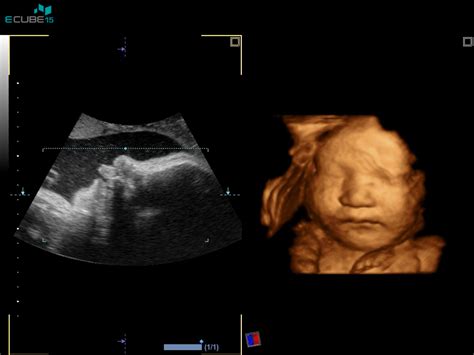

Nuhalna svetlina je v bistvu tekočina, ki se nabere pod kožo na vratu ploda v zgodnji nosečnosti. Povečana količina te tekočine lahko nakazuje na povečano tveganje za kromosomske nepravilnosti. Merjenje nuhalne svetline se izvaja z ultrazvokom in ga spremljajo še drugi parametri, kot sta merjenje nosne kosti in pretok skozi srce ploda, ter v kombinaciji z biokemičnimi preiskavami materine krvi (dvojni ali trojni hormonski test) omogoča izračun verjetnosti za določene genetske napake.

Ključnega pomena pri izvajanju nuhalne svetline je izbira ustreznega časovnega okvira. Kot je poudarjeno v medicinskih priporočilih, je ta preiskava najprimernejša med 11. in 13. tednom nosečnosti ter 6. dnem. To obdobje je izbrano zaradi bioloških značilnosti ploda, ki v tem času omogočajo natančno merjenje nuhalne svetline in drugih parametrov. Po 14. tednu nosečnosti se nuhalna svetlina namreč začne naravno zmanjševati, kar lahko vpliva na zanesljivost rezultatov.